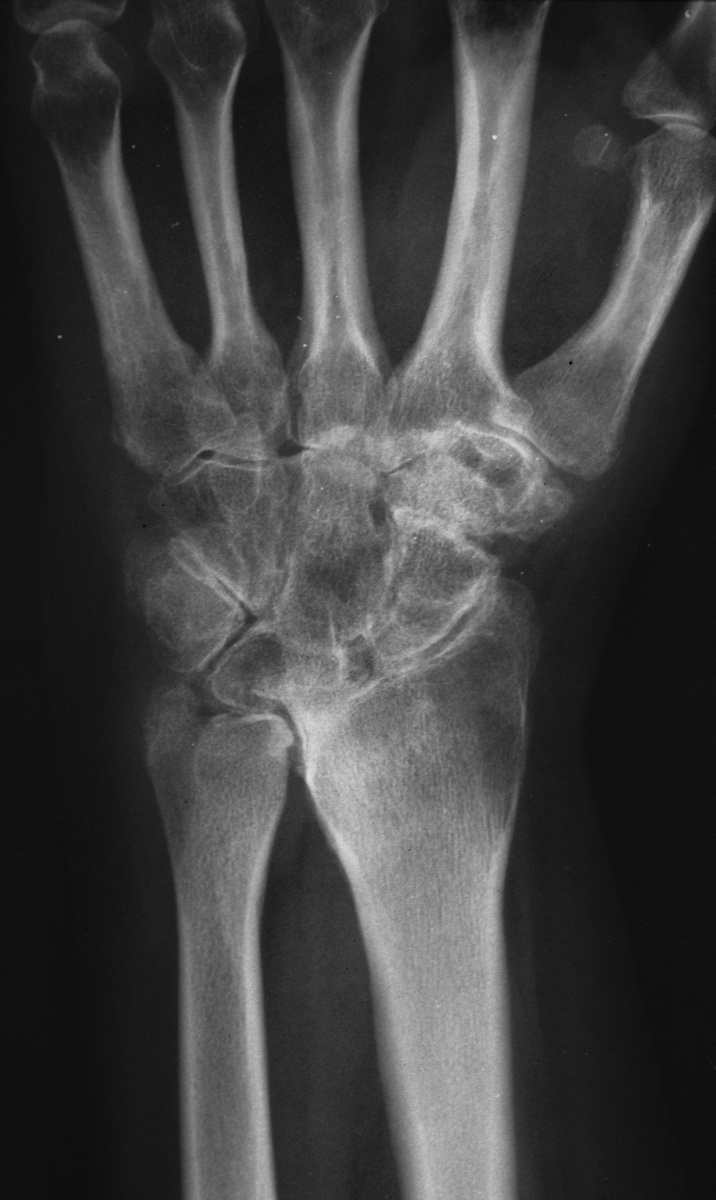

| This woman in her 30's presented with left wrist pain and was found to have inflammatory osteoarthritic changes throughout her wrist, distal radioulnar joint and thumb basal joint. Blood tests were normal, including rheumatoid factor, antinuclear antibody, sedimentation rate, uric acid, and complete blood count. She was treated with nonsteroidal oral antiinflammatory medication and splints. |

| Initial Films: |

| She had progressive deterioration over two years with worsening pain and instability. |